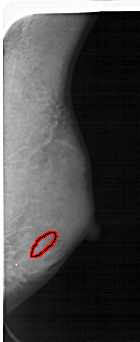

FILE: A_1482_1.RIGHT_MLO.OVERLAY

TOTAL_ABNORMALITIES 1

ABNORMALITY 1

LESION_TYPE CALCIFICATION TYPE PLEOMORPHIC DISTRIBUTION SEGMENTAL

ASSESSMENT 4

SUBTLETY 3

PATHOLOGY BENIGN

TOTAL_OUTLINES 1

BOUNDARY